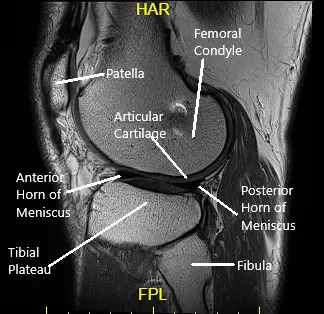

The knee joint is a hinge joint composed of the thigh bone (femur), shin bone (tibia), fibula, and kneecap (patella). The ligaments, cartilage, and menisci work together to provide stability and allow smooth movement.

- Articular cartilage cushions and protects the bones.

- Menisci serve as shock absorbers between the femur and tibia.

- Ligaments, including the ACL, PCL, MCL, and LCL, stabilize the knee by preventing excessive movement.